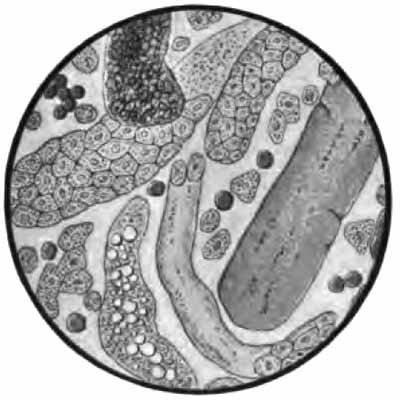

The more important structures to be seen in unstained sputum are: elastic fibers, Curschmann's spirals, [p. 27] Charcot-Leyden crystals, fibrinous casts, the ray fungus of actinomycosis, and molds. Pigmented cells, especially the so-called "heart-failure cells" (p. 43), are also best studied without staining (Plate II, Fig. 1).

Sputum from a case of actinomycosis

FIG. 8.—Sputum from a case of actinomycosis; stained (Jakob).

5. Actinomyces Bovis (Ray-fungus).—In the sputum of pulmonary actinomycosis and in the pus from actinomycotic lesions elsewhere small, yellowish, "sulphur" granules can be detected with the unaided eye. The fungus can be seen by crushing one of these granules between slide and cover, and examining with a low power. It consists of a network of threads having a more or less radial arrangement, those at the periphery presenting club-shaped extremities (Fig. 8). This organism, also called Streptothrix actinomyces, apparently stands midway between the bacteria and the molds. It stains by Gram's method.

PLATE II

Heart-failure cells in sputum

FIG. 1.—Heart-failure cells in sputum, containing blood-pigment, from a case of cardiac congestion of the lungs (Jakob).

Sputum showing tubercle bacilli

FIG. 2.—A, Sputum showing tubercle bacilli stained with carbol-fuchsin and Gabbet's methylene-blue solution (obj. one-twelfth oil-immersion); B, sputum of anthracosis, showing particles of coal-dust stained with methylene-blue (obj. one-twelfth oil-immersion) (Boston).

(1) Pus-corpuscles are present in every sputum, and at times the sputum may consist of little else. They are the polymorphonuclear leukocytes of the blood, and appear as rounded cells with several nuclei or one very irregular nucleus (Fig. 8 and Plate II, Fig. 2). They are frequently filled with granules of coal-dust and are often much degenerated. Such coal-dust-laden leukocytes are especially abundant in anthracosis, where angular black particles, both intra- and extra-cellular, are often so numerous as to color the sputum (Plate II, Fig. 2, B). Occasionally mononuclear leukocytes are present.